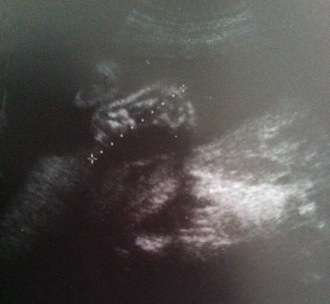

Frühling? Was bitte ist das denn jetzt? - Tagebücher aus der Schwangerschaft von Christina aus Neuss

Eine neue wunderbare, aufregende und vielleicht auch lang erwartete Lebenszeit beginnt. Für unsere Tagebücher-Blogs haben wir immer 3-4 schwangere Frauen in unterschiedlicher Schwangerschaftsphase, die in freudiger Erwartung über jede Woche dieser spannenden Zeit schreiben, uns und die vielen tausend Follower:innen daran teilhaben lassen und damit unvergessliche Momente schaffen.